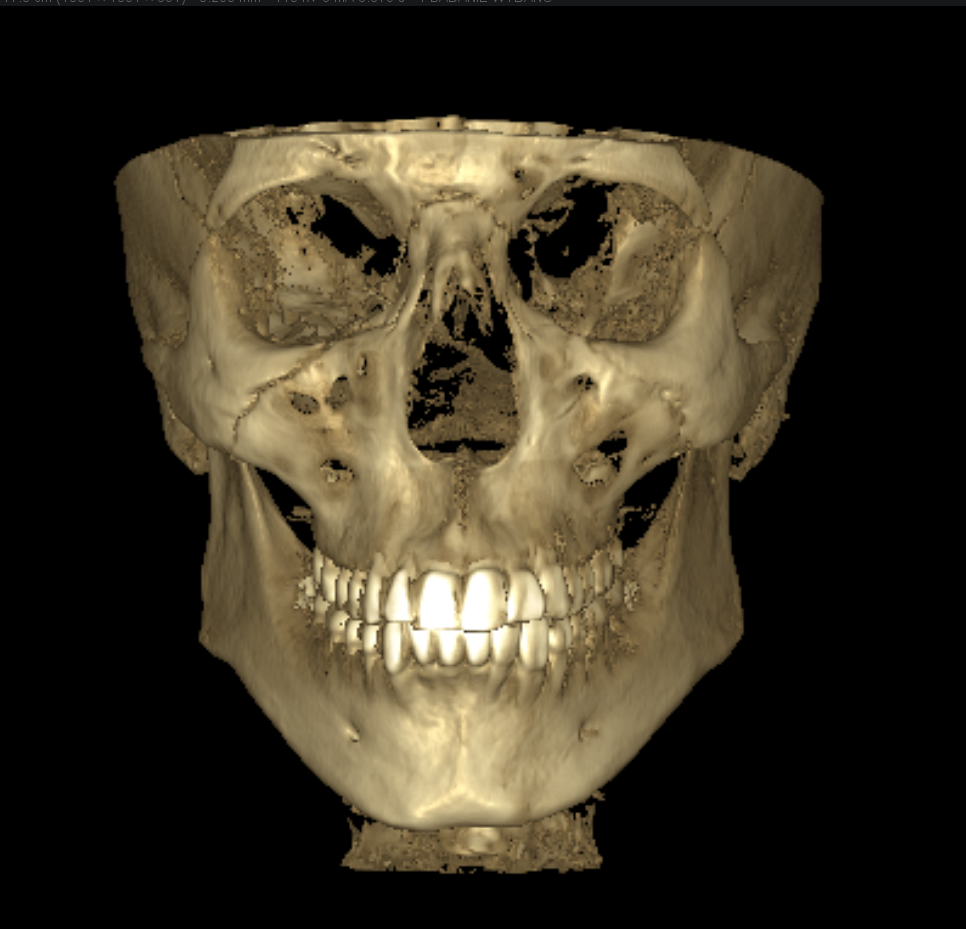

mandibular plane angle definitely not ideal